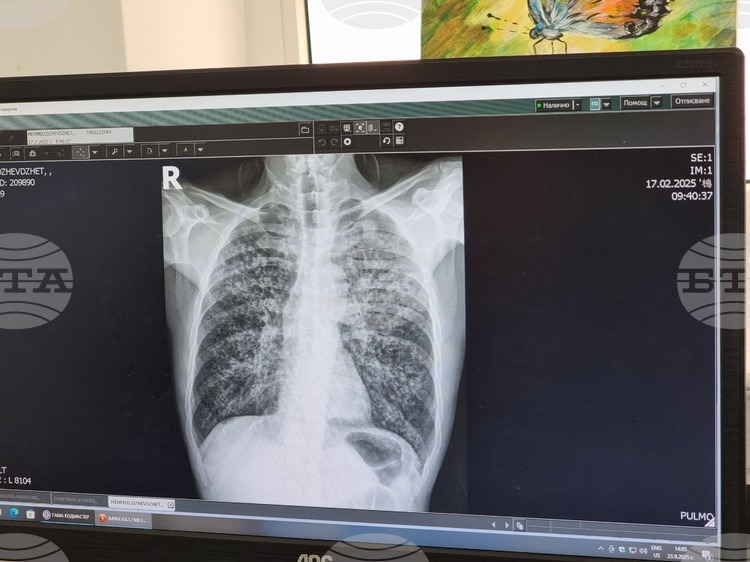

Прегледите и всички дейности по кампанията са безплатни за участниците, независимо дали са здравноосигурени. Програмата включва попълване на анкета, медицински преглед и консултации със специалисти. При необходимост ще се правят и допълнителни изследвания като проба Манту и рентгенография на белите дробове.